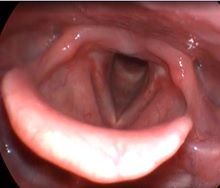

Клинический пример №2. Хирургическое лечение двустороннего паралича гортани с использованием лазера 445 нм.

Лечение данных пациентов в нашей клинике проводится по разработанному методу Кривопаловым А.А., д.м.н. зав. НИО патологии верхних дыхательных путей. Данная методика себя очень хорошо зарекомендовала.

После операции воспалительные проявления со стороны голосовой складки слабо выражены. Через месяц после операции пациенты готовы к следующему этапы реабилитации – занятие с фонопедом.

Рис 2А. Двусторонний паралич гортани. До операции.

Рис 2Б Двусторонний паралич гортани. 7 сутки после операции

Рис 2В Двусторонний паралич гортани. 1 месяц после операции